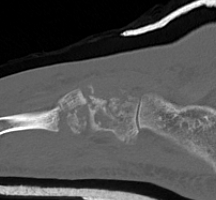

CT

cubcubcub